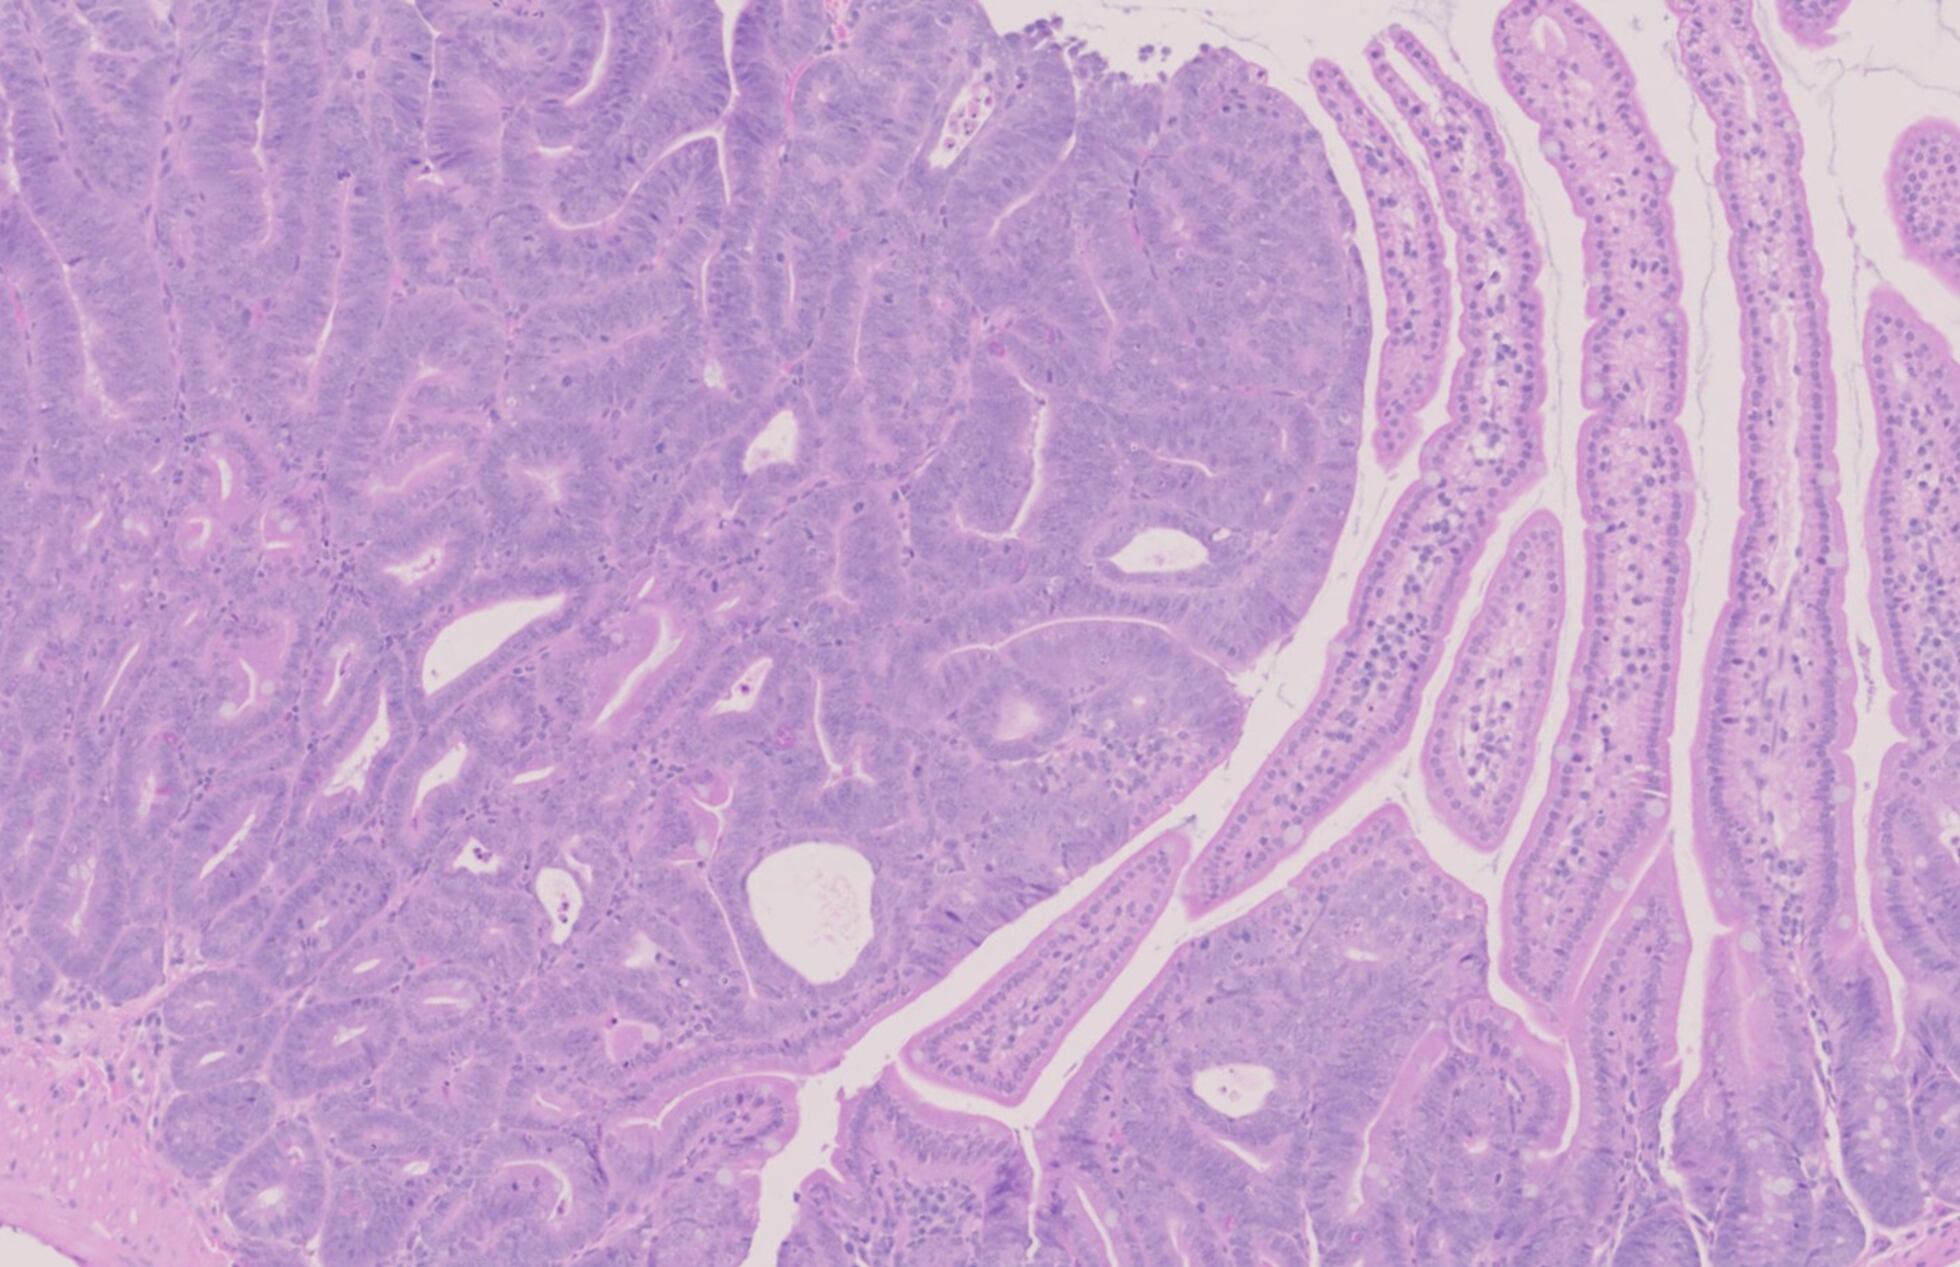

493 kediye ait tümör ve sağlıklı doku örneklerini inceleyen ekip, “kedilerde kanseri yönlendiren genleri tanımlamak ve onların onkogenomunu ortaya çıkarmak” amacıyla yola çıktı.

Bu genler, insan kanserinde rol oynayan yaklaşık 1.000 genle benzer yapı ve işleve sahip. Araştırmacılar; osteosarkomdan pankreas adenokarsinomuna, meme kanserlerinden diğer tümör türlerine kadar 13 ana tümör tipinden örnek topladılar.

Örneğin meme kanseri: Çalışma, agresif meme kanseri türlerine yol açan yedi geni belirledi. Bunlar arasında en yaygın olanı FBXW7 geni.

Kedilerdeki tümörlerin yarısından fazlasında bu gende mutasyon bulunuyor. Özellikle “üçlü negatif meme kanseri” (triple-negative breast cancer) olarak bilinen agresif alt tür, genç kadınlarda görülen bir hastalık olarak biliniyor.

Kedilerde ise bu tür çok daha sık görülüyor ve oldukça agresif seyrediyor.